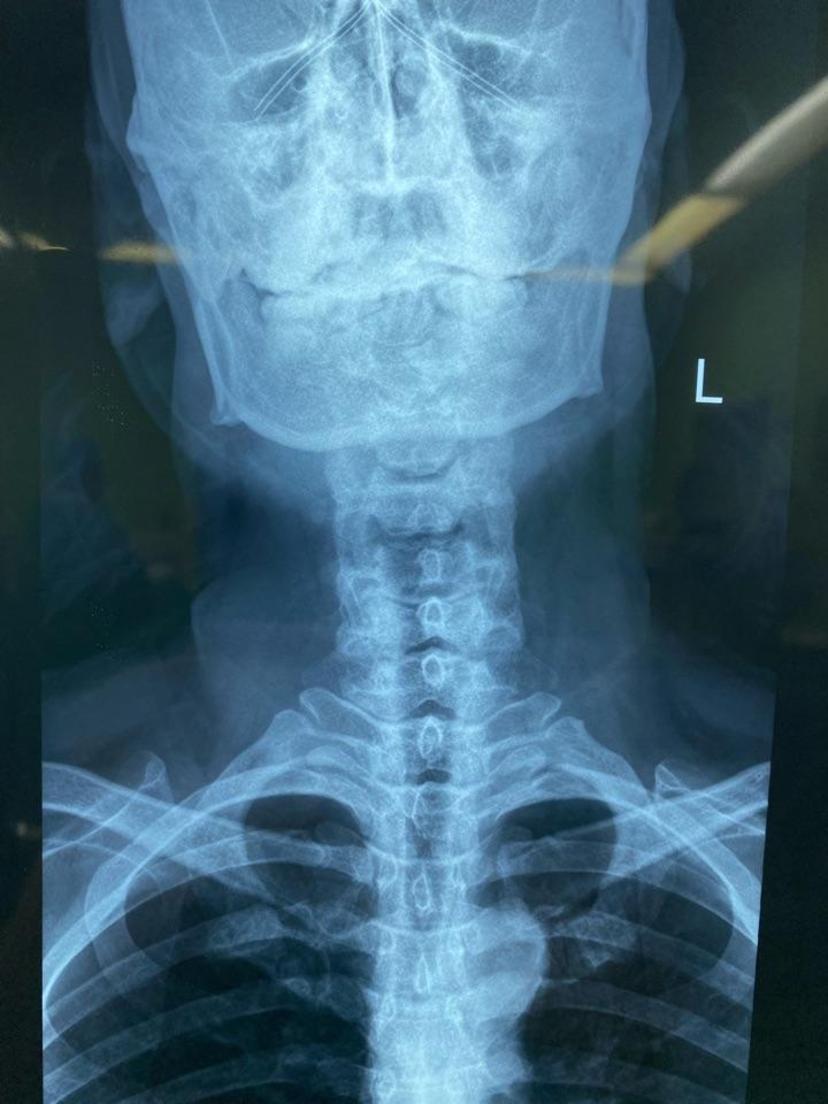

颈椎X线示:由于手臂肩膀疼痛,头偏向一侧